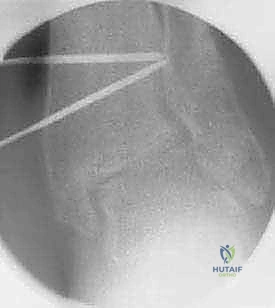

باستخدام أدوات قطع عظمية دقيقة جداً (مناشير جراحية متأرجحة)، وتحت توجيه جهاز الأشعة السينية المباشر في غرفة العمليات (C-arm)، يتم إحداث القطع في عظم الظنبوب في المكان المخطط له مسبقاً، مع الحفاظ على جزء بسيط من القشرة العظمية في الجهة المقابلة لتعمل كمفصلة (Hinge).